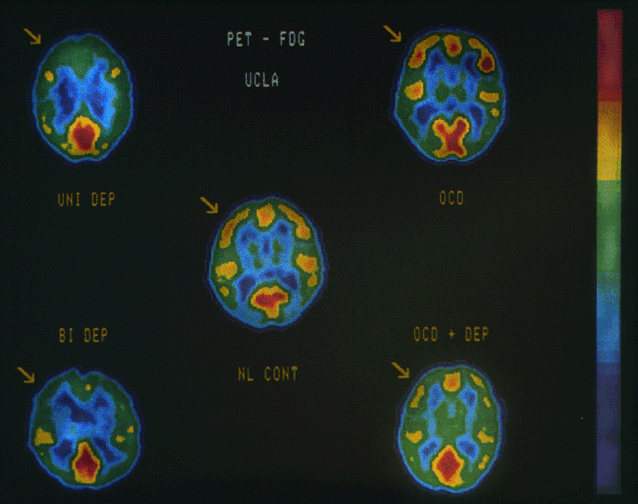

| Positron emission tomographic scans demonstrating glucose metabolic rate of each area of brain, divided by that of whole brain (red>yellow>green>blue). Scans are from five middle-aged women and illustrate findings in left dorsal anterolateral prefrontal cortex (arrows). NL CONT indicates normal control; UNI DEP, unipolar depression; BI DEP, bipolar depression; OCC, obsessive-compulsive disorder without secondary major depression; and OCD+DEP, obsessive-compulsive disorder with secondary major depression. Depressed patients show similar reduced prefrontal metabolism. With permission from Baxter et al. 1989 (7). |